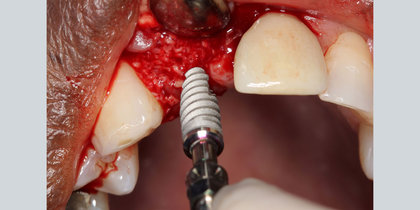

• A Glidewell HT is immediately placed into the extraction socket of a maxillary central incisor. thumbnail image

Extraction with Immediate Placement

A Glidewell HT is immediately placed into the extraction socket of a maxillary central incisor.

• Tooth #10 is immediately replaced with a Glidewell HT Implant, leading to an esthetic final restoration. thumbnail image

Tooth #10 is immediately replaced with a Glidewell HT Implant, leading to an esthetic final restoration.

• Glidewell HT Implants are immediately placed into extraction sites in the areas of tooth #3 & #4. thumbnail image

Glidewell HT Implants are immediately placed into extraction sites in the areas of tooth #3 & #4.